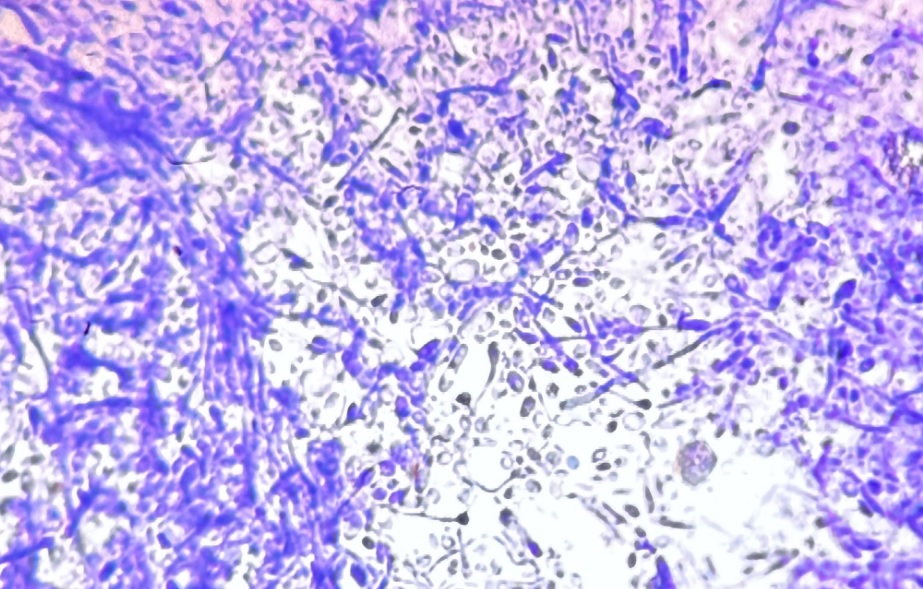

Un nou studiu european privind sănătatea arată că Candidozyma auris – o ciupercă periculoasă, rezistentă la medicamente – se răspândește rapid în spitalele de pe continent. Cazurile și focarele sunt în creștere, unele țări înregistrând în prezent o transmitere locală continuă.

Oamenii de știință au izolat pentru prima dată C auris din urechea unui pacient japonez în 2009. De atunci, s-a răspândit în spitalele din peste 40 de țări, relatează The Idenpendent.

Ciuperca provoacă de obicei doar infecții ușoare la persoanele sănătoase, dar la pacienții cu sistemul imunitar slăbit, poate fi mortală, în special atunci când pătrunde în fluxul sanguin și în organele vitale. Ciuperca afectează în principal pacienții grav bolnavi, răspândindu-se de la piele în fluxul sanguin și organe. Între 30-60% dintre pacienții infectați mor. Ciuperca este rezistentă la aproape toate medicamentele și se lipește de suprafețe ca o lipitoare – aproape imposibil de eliminat cu dezinfectanții obișnuiți.

C auris se răspândește în principal în spitale prin contact direct cu persoane infectate sau suprafețe contaminate. Ciuperca produce proteine numite adezine care o ajută să se lipească de suprafețe, făcând-o foarte greu de îndepărtat.